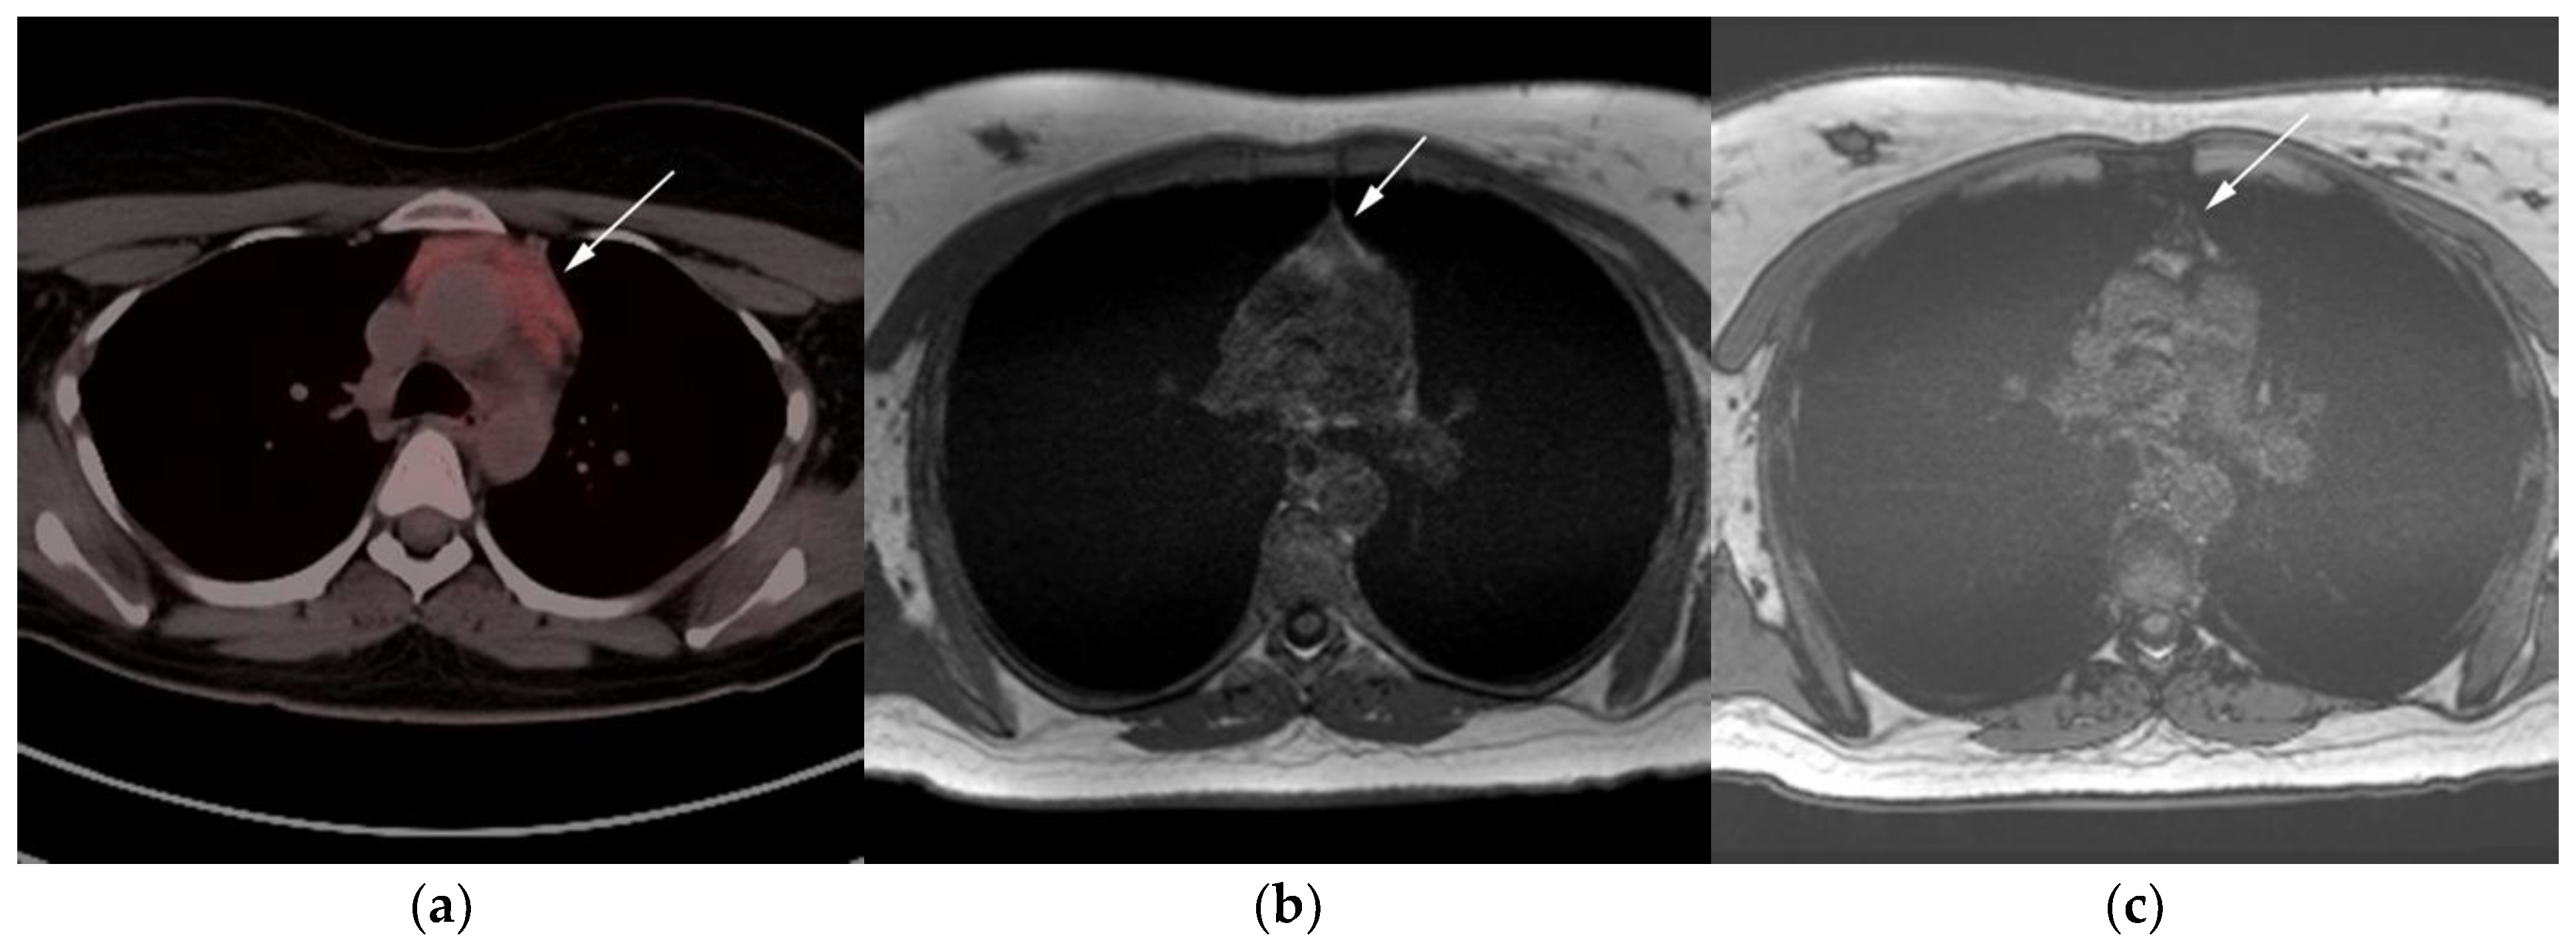

Figure 6.

Imaging in a different patient with known diagnosis of primary mediastinal B-cell lymphoma. (a) Axial FDG PET/CT images show the hypermetabolic anterior mediastinal mass (white arrows), and there is also central areas of absent metabolic activity within the mass (red arrow), correlating with areas of fibrosis, a finding that is essential in prebiopsy planning to avoid false negative results. (b) Axial FDG PET/CT images show hypermetabolic right upper paratracheal nodes (white arrows) and several additional hypermetabolic pulmonary and pleural-based nodules within right upper lung (red arrows). (c) H&E section shows that the tumor is composed of large, atypical cells with reniform or multi-lobulated nuclei with abundant clear cytoplasm. Note the lymphoma cells are compartmentalized by the prominent sclerotic bands of fibrosis. (Original magnification 400x, H&E stain).

The use of 18F-FDG PET/CT is essential in the evaluation of patients with PMLBCL to reveal sites of disease not visible on CT and to provide more accurate staging and radiation field planning (Figure 6). 18F-FDG PET/CT may also be beneficial for restaging after chemotherapy and/or radiotherapy, or when relapse is suspected [34]. Negative 18F-FDG PET/CT after two or four cycles of chemotherapy has a negative predictive value and may predict excellent outcome in patients, achieving complete response without relapse. Patients who have residual activity equal to or higher than liver activity after immunochemotherapy treatment are more likely to relapse. In such instances, the addition of radiotherapy to the treatment regimen should be considered to avoid relapse in those high-risk patients. Relapse usually occurs within 1 year and is more likely to be widespread, involving distant extranodal sites such as the CNS, liver, kidneys, adrenal glands, GI tract, ovaries, and pancreas. Late relapses are very uncommon [35]. 18F-FDG PET/CT can also efficiently assess post-treatment response, differentiating between necrotic or fibrotic tissue and residual masses containing viable tumor [33,36]. There are various potential challenges to 18F-FDG PET/CT post-treatment implementation, including false-positive results secondary to thymic rebound hyperplasia, specifically seen in the young population. This can be limited by increasing the interval between treatment and imaging. Additionally, MRI can be helpful in those cases, and high signal on T1 in phase imaging with loss of signal on the out of phase sequences is consistent with thymic rebound hyperplasia (Figure 7 and Figure 8) [34,37].